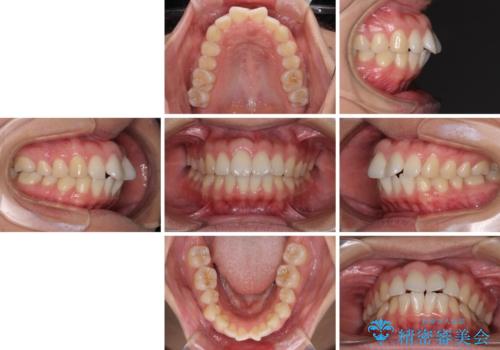

- 前歯の出っ歯と口元の閉じにくさを気にして来院された患者様です。

口元を積極的に引っ込めるために、上下左右の小臼歯4本を抜歯することとしました。

4本の歯を抜歯したことで、飛び出していた口元が引っ込み、横顔が大きく改善されました。

咬み合わせが悪化することのないようにスペースを閉じていくことができ、比較的スムーズに治療を進めることができました。